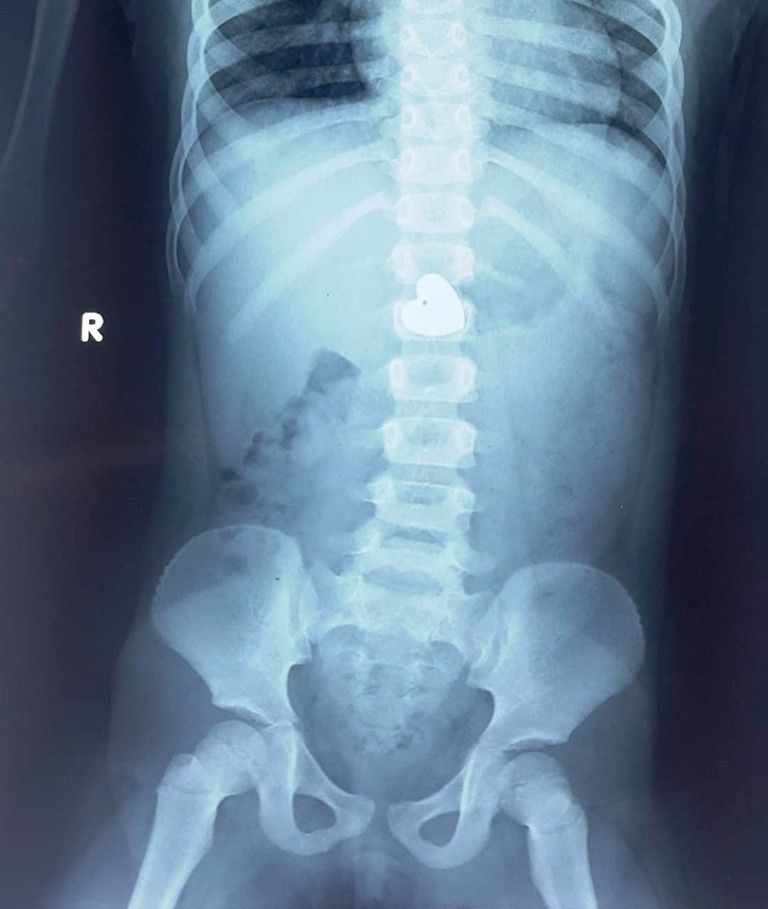

Cầm mặt dây chuyền chơi, bé gái nuốt luôn vào bụng ảnh 1Mặt dây chuyền nằm sâu trong bụng (ảnh: BVCC)

Tại đây, BS CK1 Lê Đức Lộc - thành viên ê kíp nội soi tiêu hóa BV Nhi đồng thành phố cho biết, hình ảnh chụp phim cho thấy dị vật còn nằm trong bụng. “Các bác sĩ tiếp tục kiểm tra lại để xác định vị trí và xác suất làm nội soi gắp dị vật. Nếu dị vật đã xuống ruột và có nguy cơ tắc ruột, bệnh nhi sẽ phải chịu một cuộc mổ để lấy dị vật ra” – BS Lộc nói.